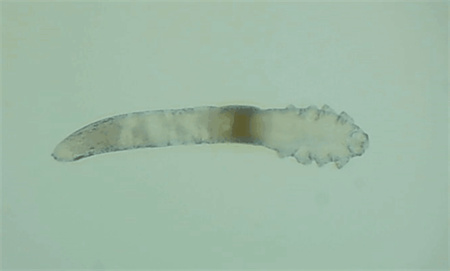

5、螨蟲檢查

從每只眼上(眼瞼)拔3根睫毛,在顯微鏡下觀察是否存在蠕形螨,以及數(shù)量多少。

如果任意一個眼瞼螨蟲數(shù)量≥3只,就需要除螨治療了。眼瞼螨蟲過多會造成機械性損傷,附帶細菌還會引起瞼緣感染,后續(xù)會有干癢、紅腫、分泌物增多、睫毛脫落等一系列問題。